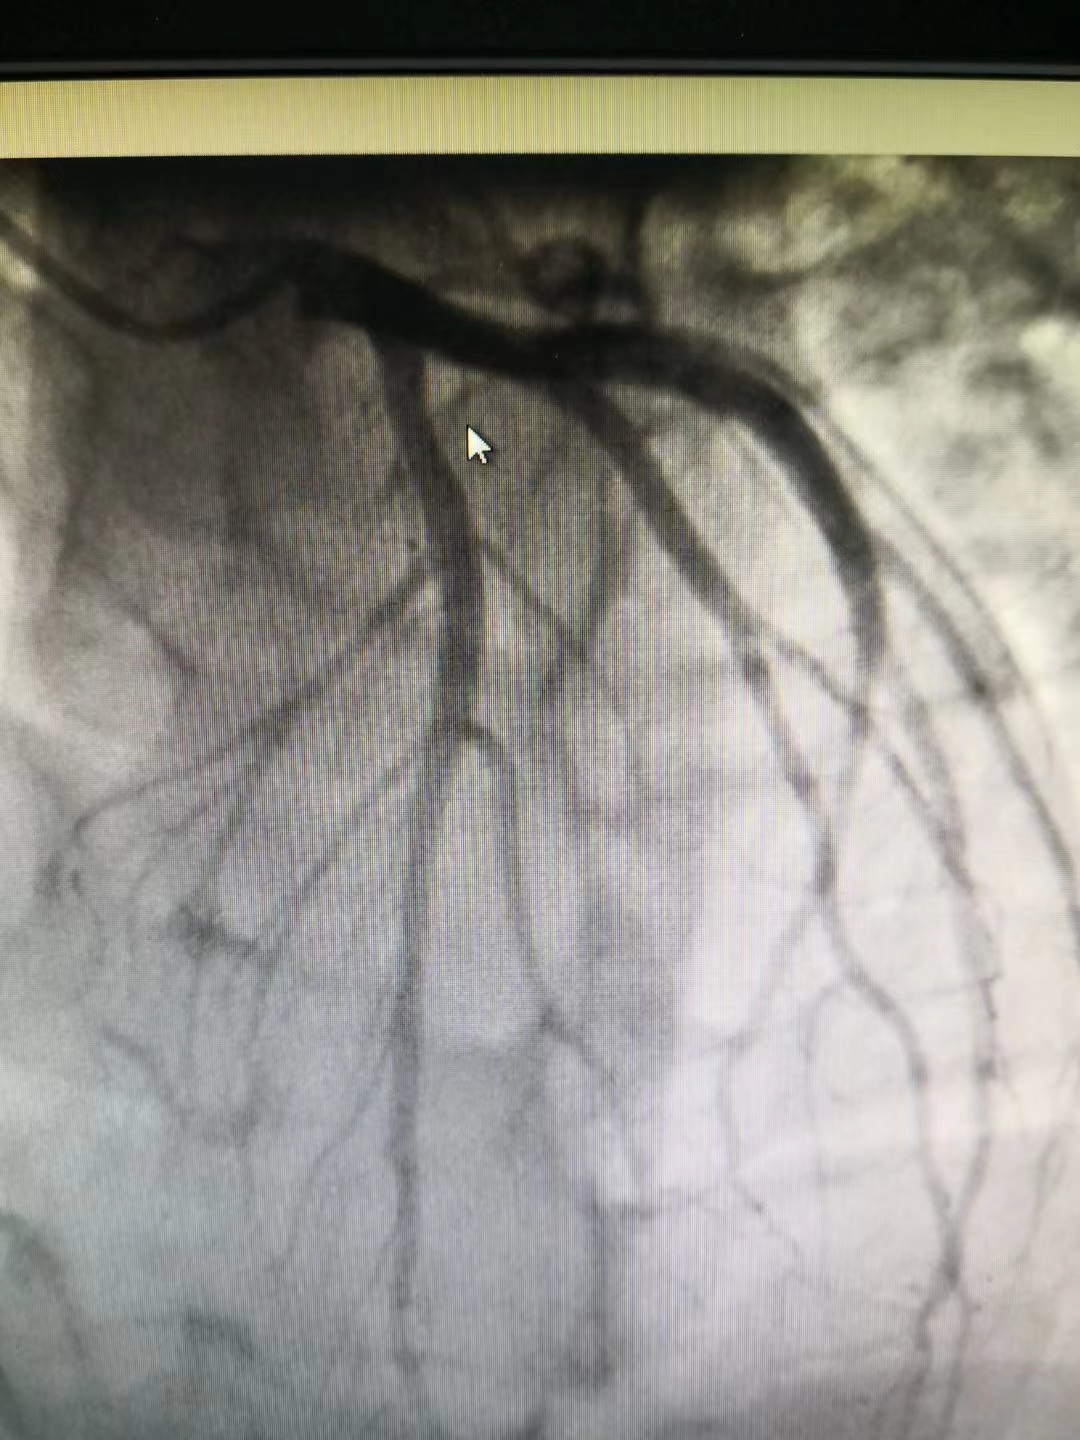

冠脈造影提示前降支近段50%局限性狹窄,遠端肌橋

小貼士:冠狀動脈造影(CAG)

冠狀動脈造影(CAG)是一項用于檢查動脈血管是否正常的輔助檢查,是診斷冠心病的有效方法之一。將導管經(jīng)大腿股動脈或其它周圍動脈插入送至升主動脈,再插入左或右冠狀動脈口,注入造影劑,使冠狀動脈顯影。CAG能較明確地揭示冠狀動脈的解剖畸形及其阻塞性病變的位置、程度與范圍,是目前唯一能直接觀察冠狀動脈形態(tài)的論斷方法,醫(yī)學界稱其為“金標準”。